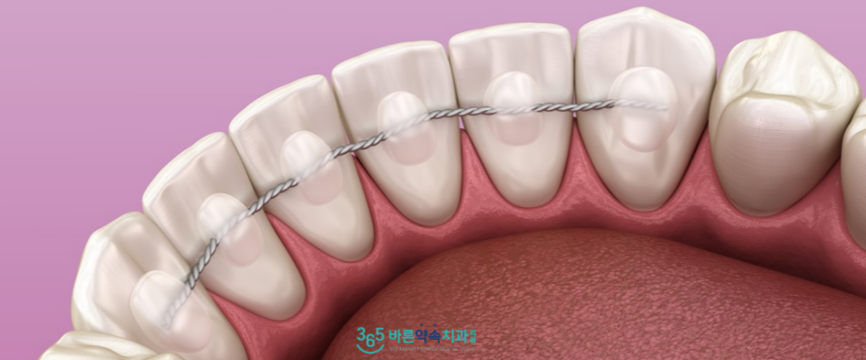

교정치료가 마무리된 후에도

고르게 배열된 치열이 흐트러지지 않도록

치아의 뒷면에

얇은 철사를 붙여드렸으며